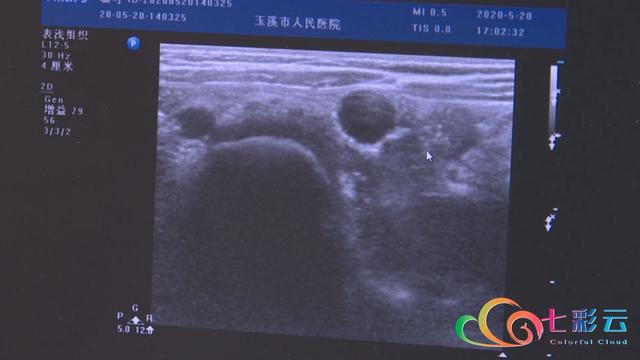

彩色颗粒的海洋宝宝对孩子有非常大的吸引力,极易被误食,误食后不慎堵塞呼吸道,可能会导致窒息,要是进入了消化道,可能会造成肠管扩张、肠梗阻,严重时甚至造成肠坏死、肠穿孔,危及生命。

据了解,“海洋宝宝”其实是一种吸水性树脂,里面所含的丙烯腈或丙烯酸酯都有一定毒性,是绝对不能给孩子当做玩具的。如果发现孩子误食,家长第一时间应该带孩子去医院就医。

《警惕!玉溪多名儿童误食这东西,险些夺命!B超触目惊心…》